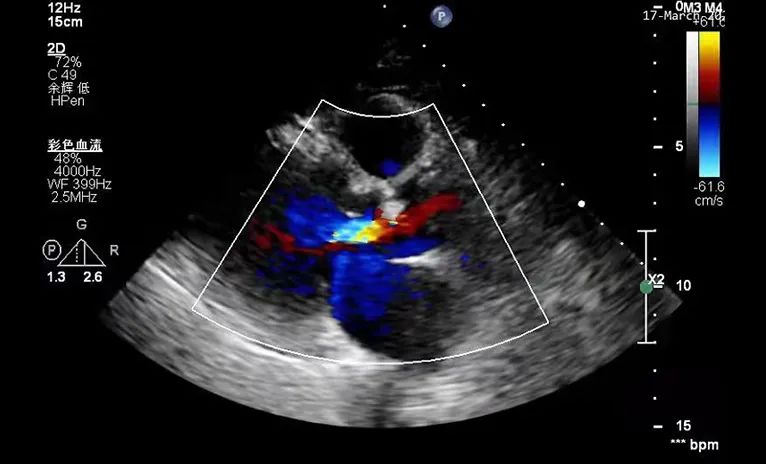

超声检查

彩超证实王女士的确存在重度主动脉狭窄合并轻-中度主动脉瓣关闭不全,且主动脉瓣跨瓣压差高达74mmHg。高度狭窄的主动脉瓣,导致王女士心脏左心室射血到主动脉的过程受阻,久而久之造成心力衰竭。

术后超声

术后超声科叶华容主任在手术室为患者进行术后评估,实时超声显示该患者主动脉跨瓣压差由术前的74mmHg显著下降到术后的16mmHg,手术效果立竿见影,患者胸闷、气促症状明显缓解,且无传导阻滞、穿孔等并发症发生,宣告手术圆满结束。